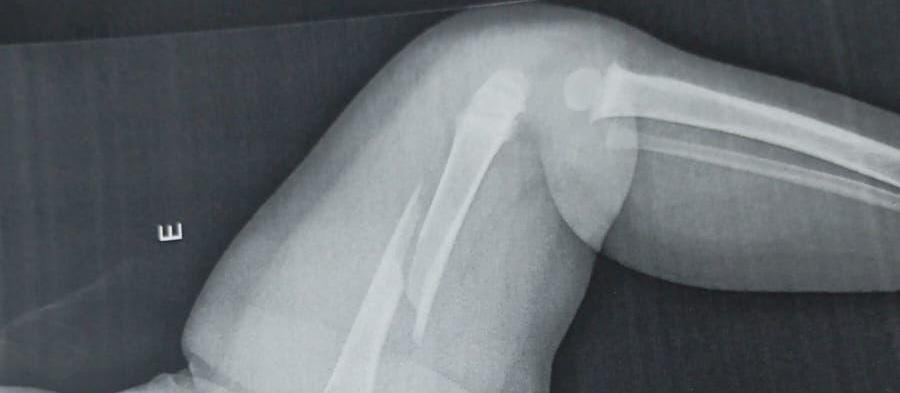

Diante da situação, a criança foi encaminhada ao hospital, onde exames constataram a fratura no fêmur. Posteriormente, Benjamin foi transferido para Maringá, passou pela UPA e depois foi encaminhado ao Hospital Municipal, onde permanece internado.

Ainda de acordo com a avó, médicos informaram que a criança também apresenta uma fratura antiga no braço, o que levantou suspeitas de agressões anteriores. Rosângela e o pai do menino acreditam que Benjamin possa ter sido vítima de violência no ambiente em que vivia com a mãe e o padrasto.